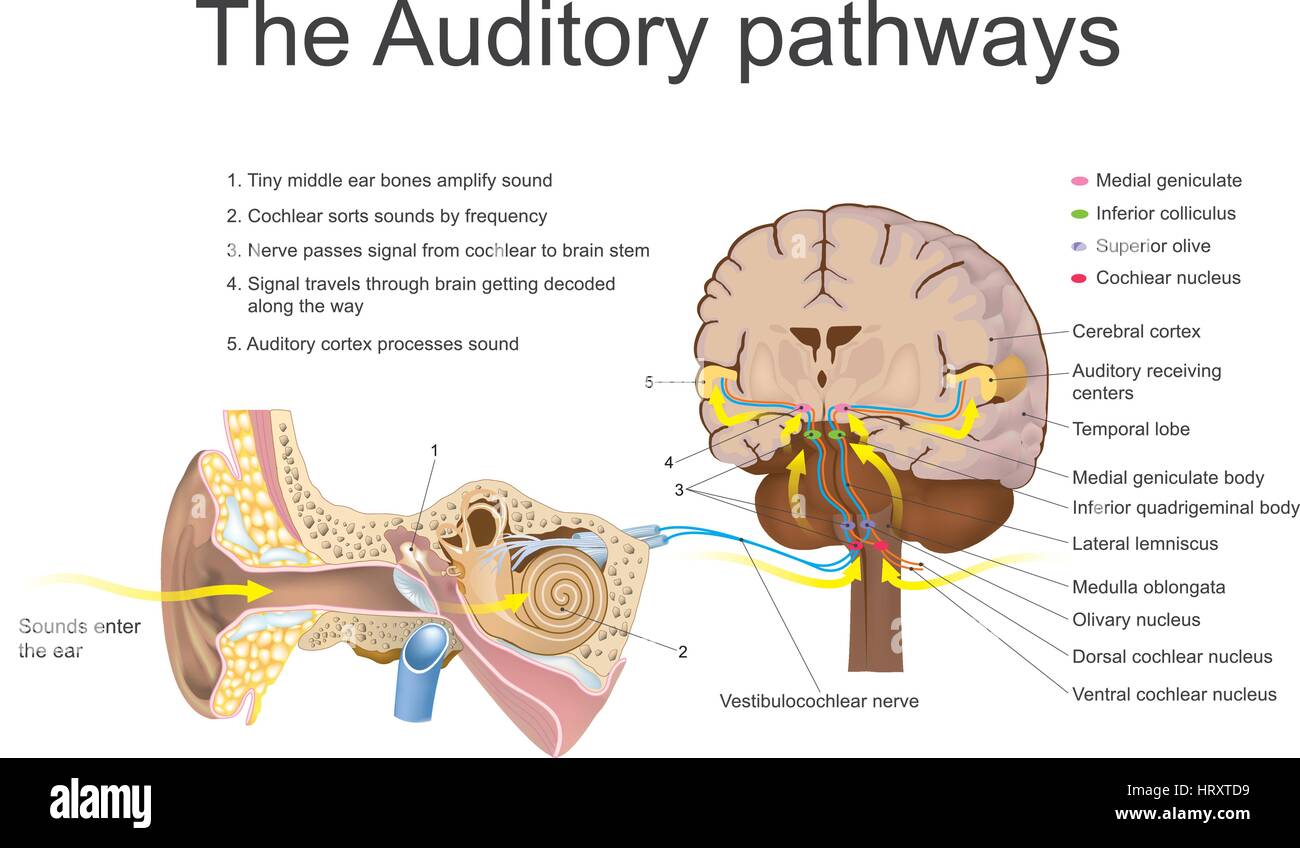

Il sistema uditivo è il sistema sensoriale per il senso dell'udito. Esso comprende sia la organi sensoriali (orecchie) e le parti uditiva del senso Illustrazione Vettorialehttps://www.alamy.it/image-license-details/?v=1https://www.alamy.it/foto-immagine-il-sistema-uditivo-e-il-sistema-sensoriale-per-il-senso-dell-udito-esso-comprende-sia-la-organi-sensoriali-orecchie-e-le-parti-uditiva-del-senso-135199605.html

Il sistema uditivo è il sistema sensoriale per il senso dell'udito. Esso comprende sia la organi sensoriali (orecchie) e le parti uditiva del senso Illustrazione Vettorialehttps://www.alamy.it/image-license-details/?v=1https://www.alamy.it/foto-immagine-il-sistema-uditivo-e-il-sistema-sensoriale-per-il-senso-dell-udito-esso-comprende-sia-la-organi-sensoriali-orecchie-e-le-parti-uditiva-del-senso-135199605.htmlRFHRXTD9–Il sistema uditivo è il sistema sensoriale per il senso dell'udito. Esso comprende sia la organi sensoriali (orecchie) e le parti uditiva del senso